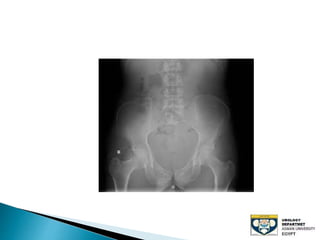

The document discusses urinary tract stones, detailing their types, causes, symptoms, and diagnostic methods. It highlights the risk factors such as infections and obstructions, with men being more commonly affected. Treatment options include various surgical methods, particularly for managing bladder outflow obstruction and lithiasis.